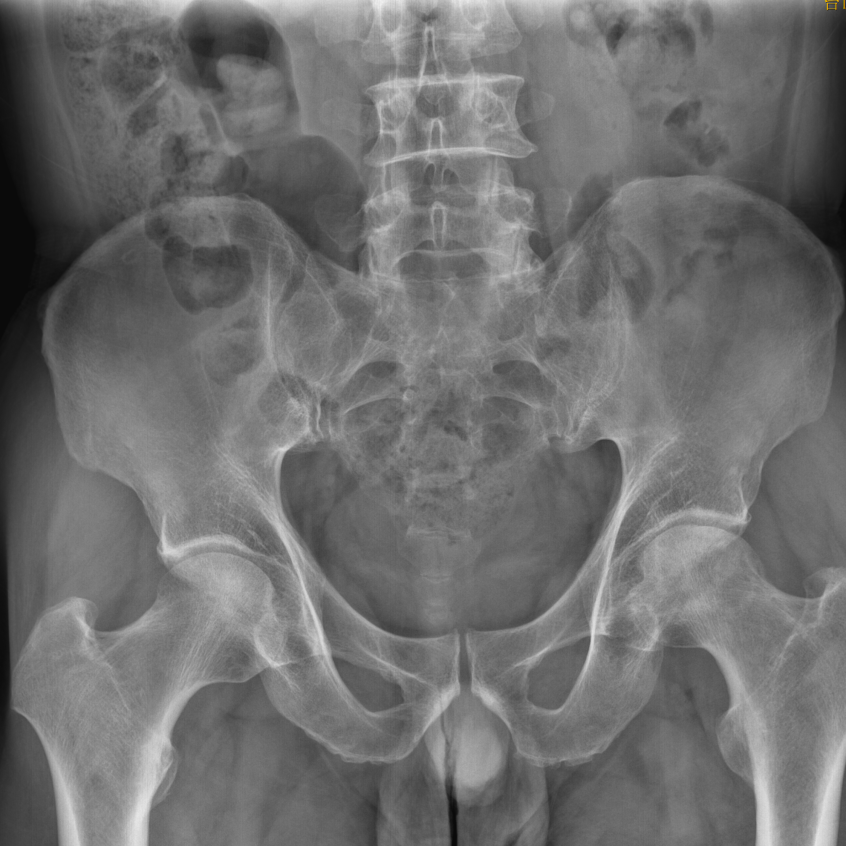

患者56岁男性,近半年来患者感双侧髋部疼痛,行走及活动后加重,疼痛主要为酸痛,向腹股沟区,大腿内侧放射,活动稍受限。病情逐渐加重,三月前曾在外院就诊,明确诊断双侧股骨头坏死,建议患者择期行髋关节置换术治疗。在此期间患者多方就医未果。后为进一步诊治,就诊我科门诊,经检查后拟诊断:1.右侧股骨头缺血性坏死(ARCO II期) 2.左侧股骨头缺血性坏死(ARCO III期)。予以收住入院。 X片及MR情况: 针对患者的情况,陈庆华副院长、陈浩波主任带领骨一科成员进行了全面分析和反复讨论。考虑患者正值壮年,且右侧股骨头坏死区未出现明显塌陷,处于Ⅱ期,适合保髋治疗,可考虑行保髋手术。目前的保髋治疗方式有很多,为此,科室团队经过反复论证,制定了详细的手术方案,决定应用结合髓芯减压、植骨、3D打印成型AVN Cage植入进行保髋治疗。 术中情况: 经过充分的术前准备,通过C形臂定位,将导针精准打入股骨头坏死区,用空心钻制作骨道至坏死区域,进行髓芯减压,并通过刮匙刮除股骨头内的坏死骨组织,然后将取出的粗隆区正常骨质植入坏死区域,最后将3D打印成型的AVN Cage植入,为股骨头坏死区提供可靠支撑。手术顺利完成,目前患者恢复良好。 不畏负重,保髋前行。我院外科团队一直深耕在股骨头坏死治疗领域,在保髋方面,从无到有,AVN Cage材料重建手术,给患者股骨头重生的希望。骨一科团队将始终牢记初心及使命,继续在股骨头坏死的保髋领域进行探索、创新!